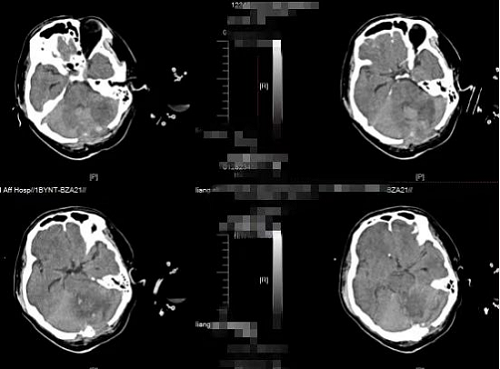

明确诊断后,各科室争分夺秒快速完善各项术前准备工作。从桂先生入院到进入手术室,耗时不到30分钟。由神经外科二区脑血管病组龙丁辉医生主刀进行手术,手术过程顺利。患者术后转入ICU,经过不间断不放弃的全力抢救后,患者的生命体征逐渐恢复到平稳状态,术后第10天转回普通病房,经过精心的术后康复治疗,患者意识清醒,出院后继续康复治疗。

图2术后CT